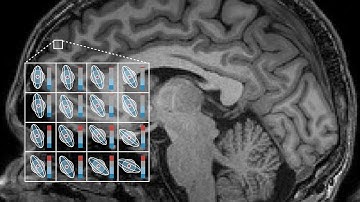

BrainMap: Brain Microstructure Imaging with Diffusion MRI